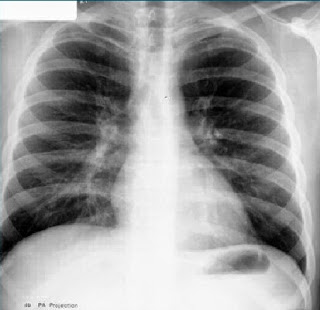

Las

enfermedades pulmonares se pueden localizar en el árbol bronquioalveolar, el intersticio y en los vasos sanguíneos o

linfáticos. Al conjunto de características relacionadas

con diversos procesos se denominan patrón radiológico pulmonar.

Podemos

tener una disminución de la densidad (hiperclaridad) bien sea de forma

localizada o difusa. Es debido a la disminución de la vascularización pulmonar

en casos de TEP masivo o hipertensión pulmonar o al aumento del espacio aéreo

(atrapamiento aéreo) como en EPOC o a ambas causas como el enfisema pulmonar.

Por

el contrario también existe el aumento de densidad pulmonar (opacidad) que

corresponde a los siguientes patrones: